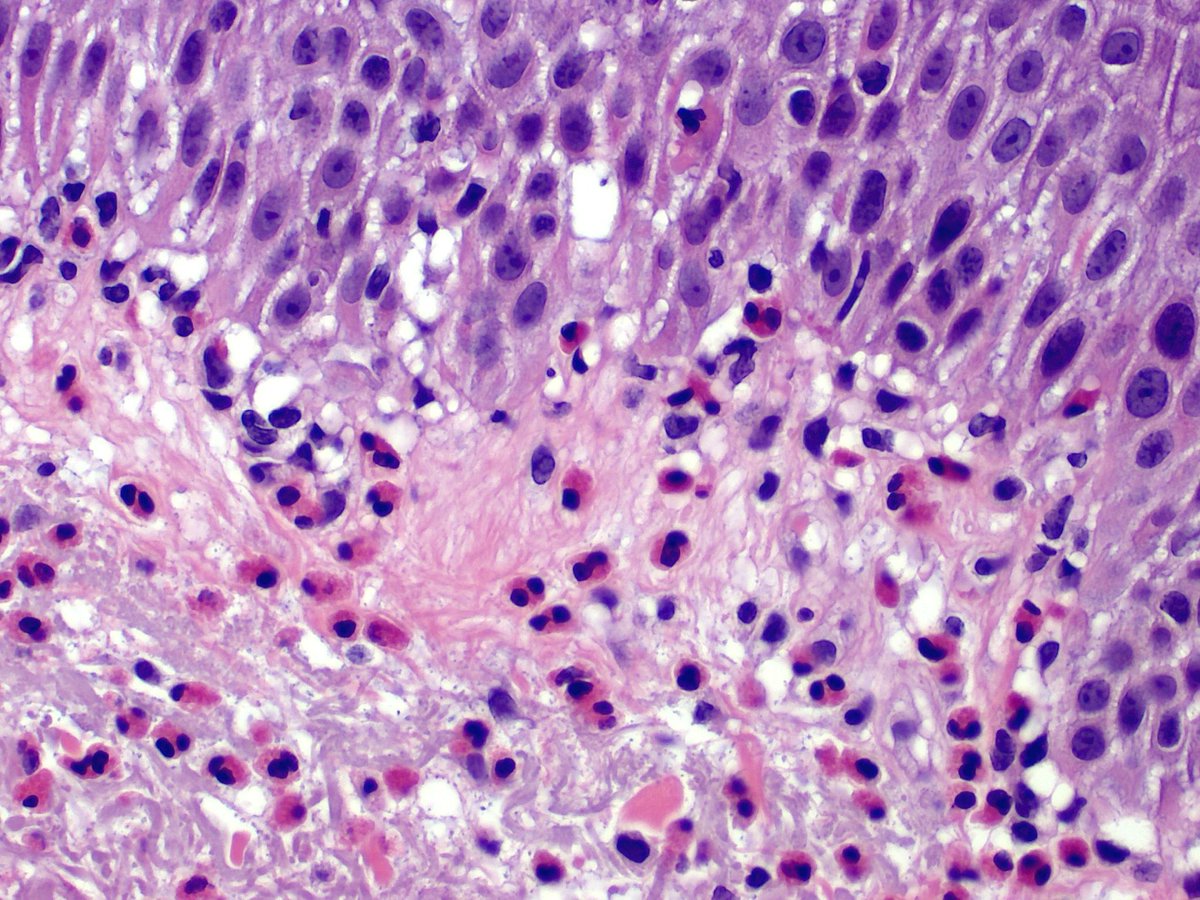

Lump on the scalp.  Easy if you use your brain, a bit tricky for those of us who only think skin deep....#dermpath #dermatology #pathology

And the answer is ... cutaneous meningioma. Quite uncommon, and easy to start thinking adnexal, melanocytic, cellular neurothekeoma if your practice stops at the fascia like me! All you need to know in: pubmed.ncbi.nlm.nih.gov/22288971/ #dermpath #pathology #dermatology